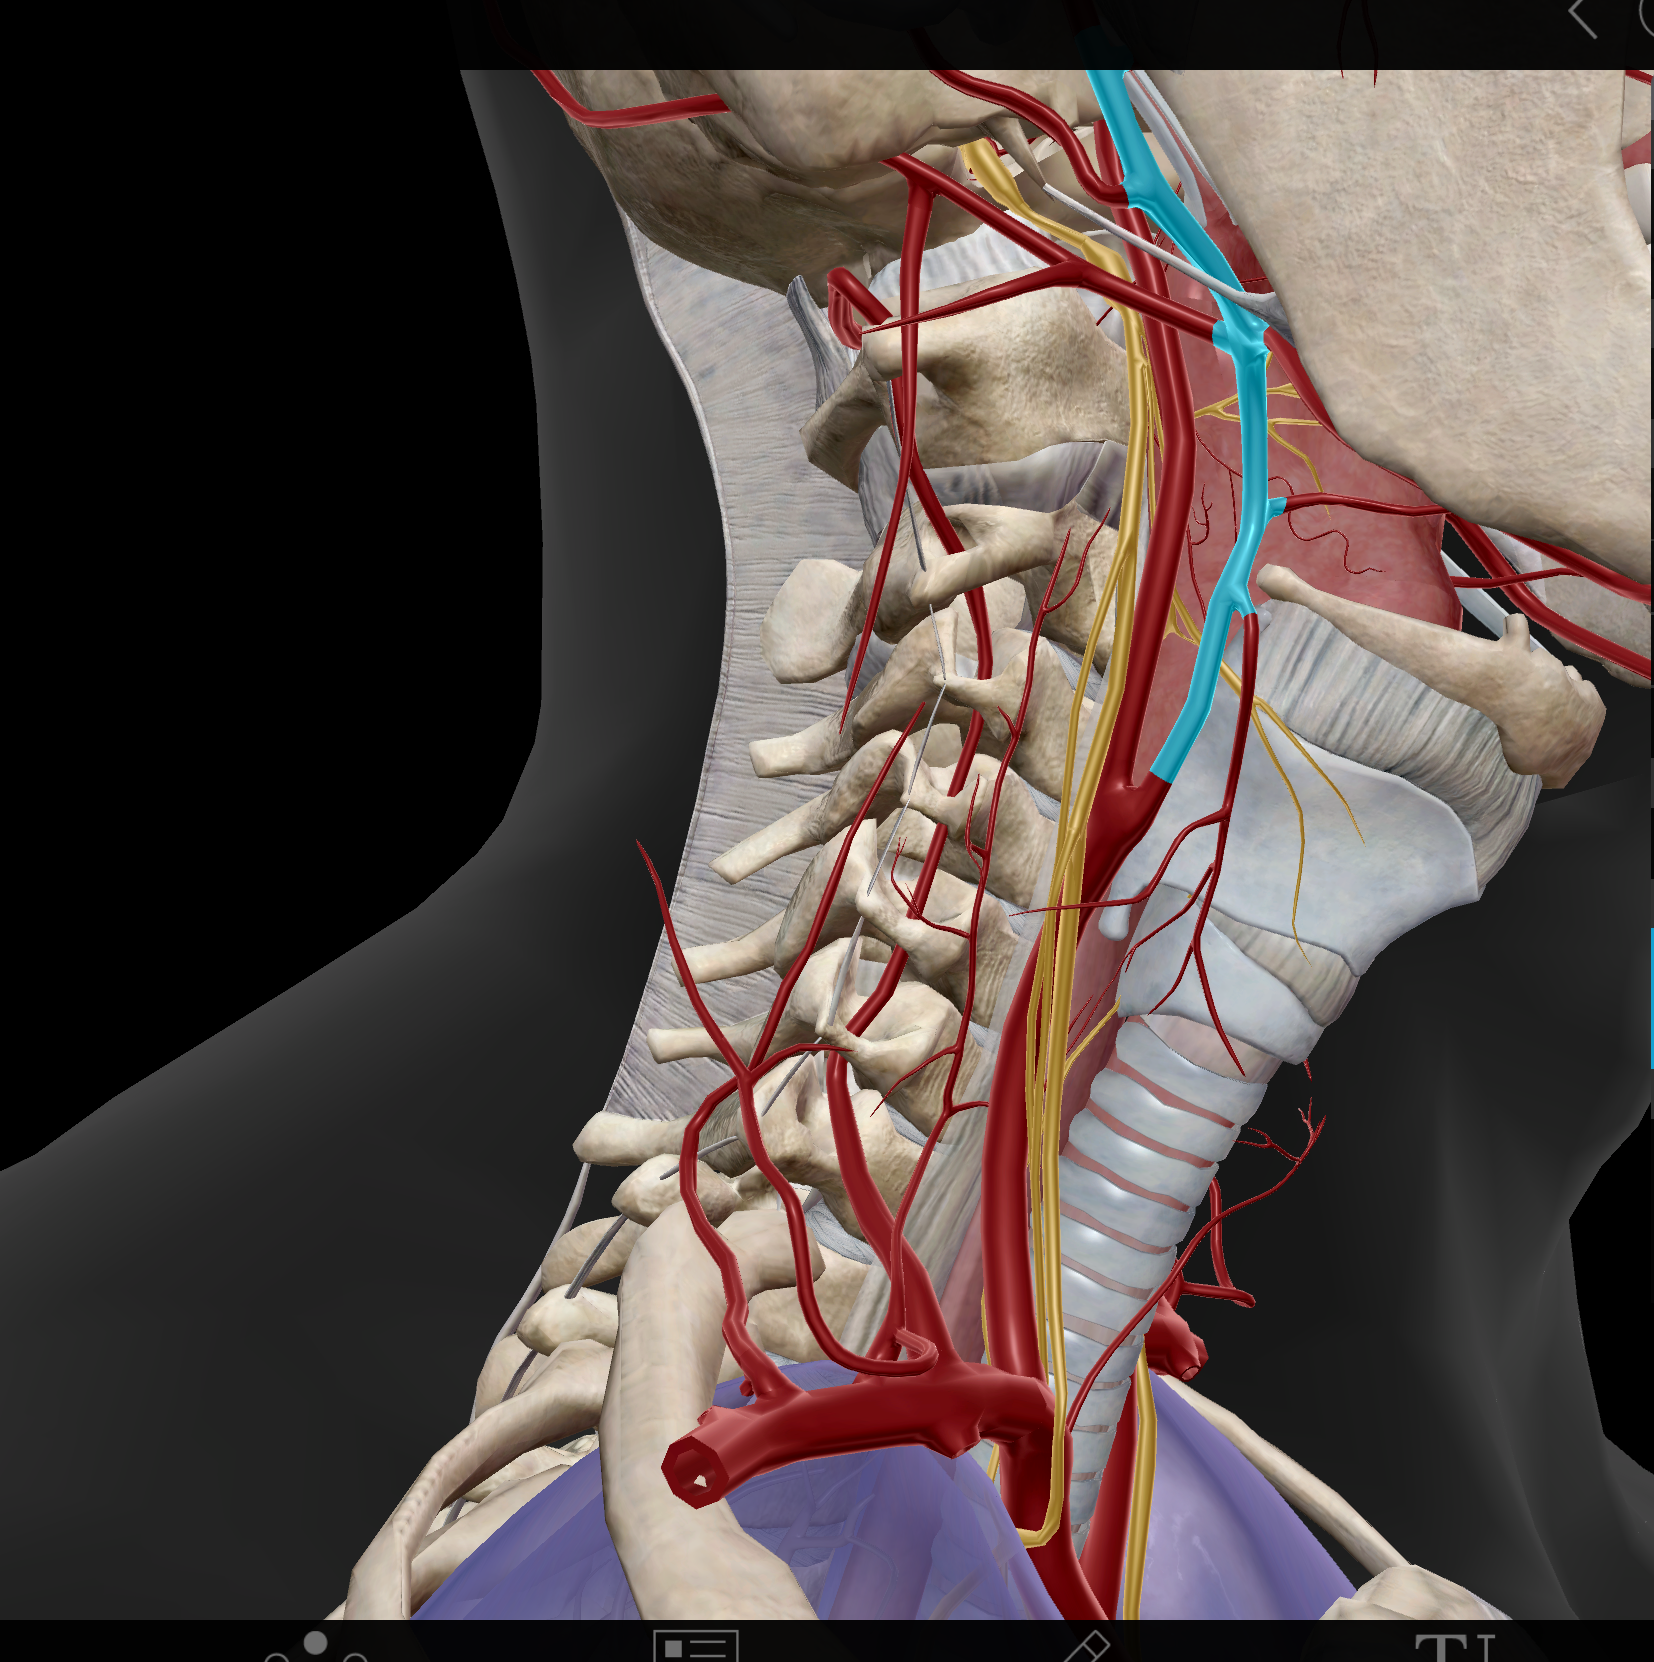

Common carotid a.(L and R)

External carotid a. (L and R)

Internal carotid a. (L and R)